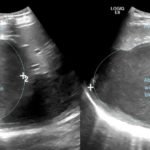

Although rare in the developed world, amebic infections are common worldwide and represent a challenging and often overlooked diagnosis. In this case, an amebic liver abscess was discovered in a 29-year-old male who presented to the emergency department (ED) complaining of right upper quadrant abdominal pain, weight loss, non-bilious/non-bloody vomiting, and diarrhea for three months. He recently traveled to India and Mexico. Point-of-care ultrasound discovered a liver mass and computed tomography (CT) confirmed the presence of a liver abscess. The case highlights the usefulness of ultrasound as an initial diagnostic tool, the importance of careful travel history in patients with suspected infectious diseases, and the initial provision of broad-spectrum coverage for bacterial and amebic pathogens for liver abscesses until the pathogen has been identified.